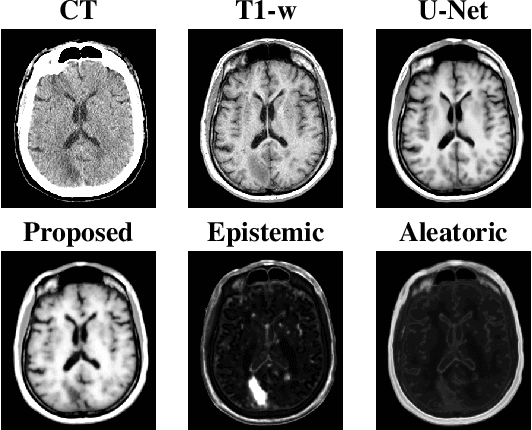

Abstract:Medical images are often used to detect and characterize pathology and disease; however, automatically identifying and segmenting pathology in medical images is challenging because the appearance of pathology across diseases varies widely. To address this challenge, we propose a Bayesian deep learning method that learns to translate healthy computed tomography images to magnetic resonance images and simultaneously calculates voxel-wise uncertainty. Since high uncertainty occurs in pathological regions of the image, this uncertainty can be used for unsupervised anomaly segmentation. We show encouraging experimental results on an unsupervised anomaly segmentation task by combining two types of uncertainty into a novel quantity we call scibilic uncertainty.